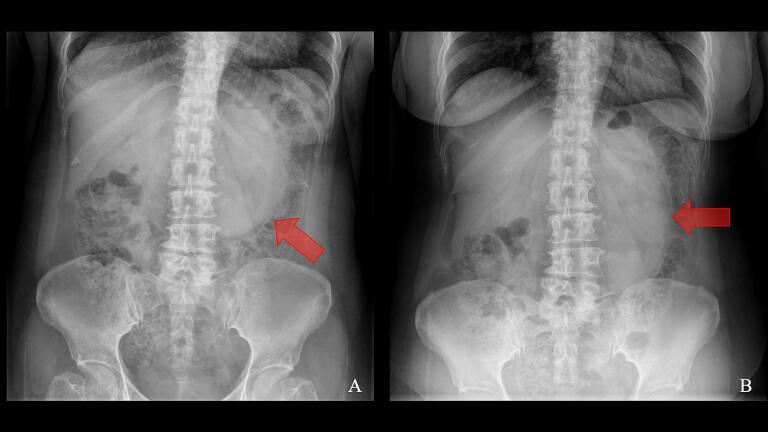

CASE PRESENTATION

We report a case of a 56-year-old woman presenting with acute small bowel obstruction due to a strangulated left paraduodenal hernia. Emergency laparoscopic surgery revealed ischemic bowel segments within the hernia sac. We utilized indocyanine green (ICG) fluorescence imaging to assess bowel perfusion intraoperatively, guiding our decision for bowel resection. The procedure involved hernia reduction, resection of non-viable bowel, and primary anastomosis, followed by hernia defect closure. Despite encountering a small bowel injury during reduction, we successfully completed the procedure laparoscopically.

病例报告

我们报告一例56岁女性因绞窄性左十二指肠旁疝出现急性小肠梗阻。急诊腹腔镜手术发现疝囊内有缺血肠段。我们术中使用吲哚菁绿(ICG)荧光成像评估肠灌注,指导我们进行肠切除的决策。手术包括疝还纳、切除无活力肠段和一期吻合,随后关闭疝缺损。尽管在还纳过程中遇到小肠损伤,我们仍成功地通过腹腔镜完成了手术。